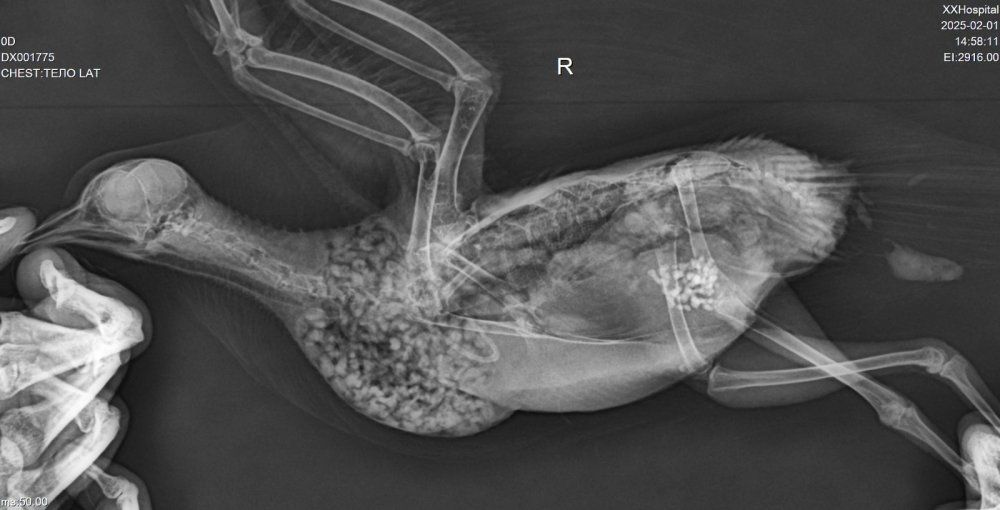

Добрый день! Были на рентгене. Травм не обнаружили. Есть застойные явления в легких, возможно, из-за отсутствия движения. Рентгенолог сказала, судя по симптомам, нельзя исключать менингит.

00072939.jpg

00072938.jpg

00072937.jpg

Рентген никакого качества.

Кроме "матового стекла" в легких и почти полностью не проглядываюшегося целома- сказать ничего не могу.

И как ставят менингит, если нет снимка черепа...

Вечер добрый! Мы наконец повторили рентген. @Zosia не могли бы взглянуть, пожалуйста?

DX001775_1.jpg

DX001775_2.jpg

DX001775_3.jpg

DX001775_4.jpg

На снимке странно выглядит зона,где должен находиться коракоид. Возможно имеем его перелом. Если это так- то понятно отсутствие возможности летать и общая вялость,т.к. это чрезвычайно болезненный перелом и опасный...

Почему на правом крыле вы видите "шишку"- непонятно. Внешне сустав (локтевой) правого крыла без изменений.

Вообще все положение тела птицы несколько "скособочено" вправо... возможно был плоский удар (машина), и имеются отечные явления

,посттравматические.

Из-за несколько скривленного положения тела на латеральной проекции (праволатеральная) позвононик странно расположен, "фрагментарно", с S-образным изгибом.

Поэтому вопрос- птица какает нормально? Т.е. стандартно порциями, а не постоянным изливом фекалий?

Череп на ВД снимке без патологий.

На лат проекции есть некие объекты, в зоне гонад/яичника, больше похожие на гранулемы яичника .

Пока кроме продолжения терапии НПВС, миорелаксантами, витаминами В6 и В12, источниками кальция- нечего добавить (по части преджполагаемой травмы).